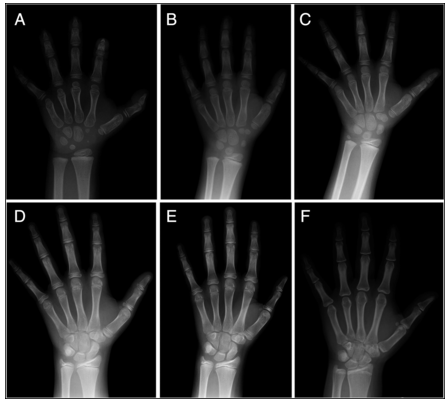

图片摘自威廉姆斯内分泌学

可以看到在婴儿期,两性的促性腺激素(LH和FSH)均有类似于青春期的脉冲式分泌